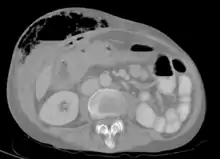

| Abdominal CT scan with right colocutaneous fistula and associated subcutaneous pneumatosis | |